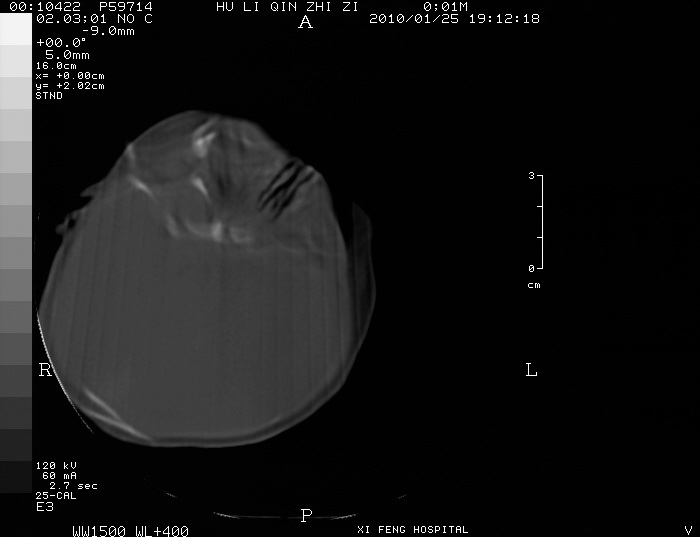

男  新生儿,曾做b超股骨长5.5厘米,疑畸形,家族中有多个身才矮小.曾孕两次,一次流产,一次宫内死亡

四肢干骺端呈喇叭口型缺损,颅骨缝增宽,支持软骨发育不全。